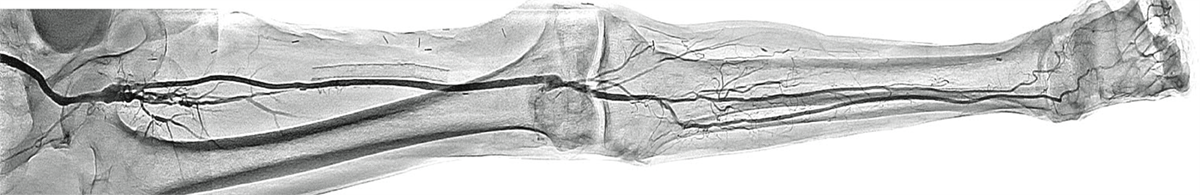

Dynamic Trace дає клініцистам можливість виконувати цифрову зйомку під час руху стола за потоком контрасту. Це зображення є прикладом панорамування від стегна до стопи

DT – це цифровий метод отримання даних, який використовується в режимі панорамування для покращення зображення судин за рахунок збільшення стиснення фону та зменшення візуалізації кісток. Ефект, схожий на DSA.

Приклад Dynamic Trace від стегна до коліна під час повздовжнього руху стола